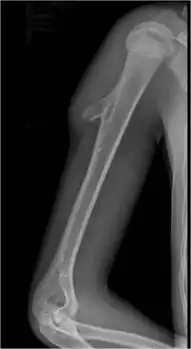

Osteochondroma, a common type of non-cancerous chondrogenic tumors

Osteochondroma[2]